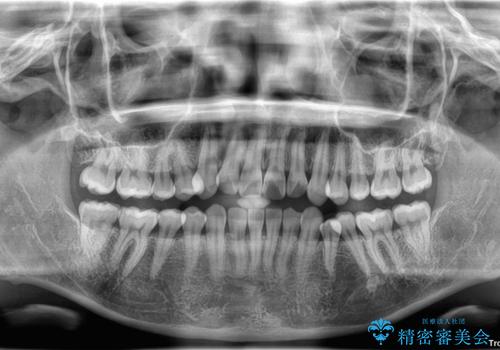

初診時、上下顎ともに歯列の不正が認められ、特に左下の小臼歯が大きく歯列から外れている状態でした。その影響により、下顎の正中が左側へシフトしており、見た目だけでなく噛み合わせにも影響が出ていました。

左下の小臼歯をきれいに歯列内へ並べるためには、まず十分なスペースの確保が必要でした。

そこで本症例では、上顎右側にアンカースクリュー(矯正用インプラント)を埋入し、そこからゴムかけ(顎間ゴム)を行うことで、下顎の正中を右方向へコントロール。

これにより、左下小臼歯がく並ぶためのスペースを確保することができました。